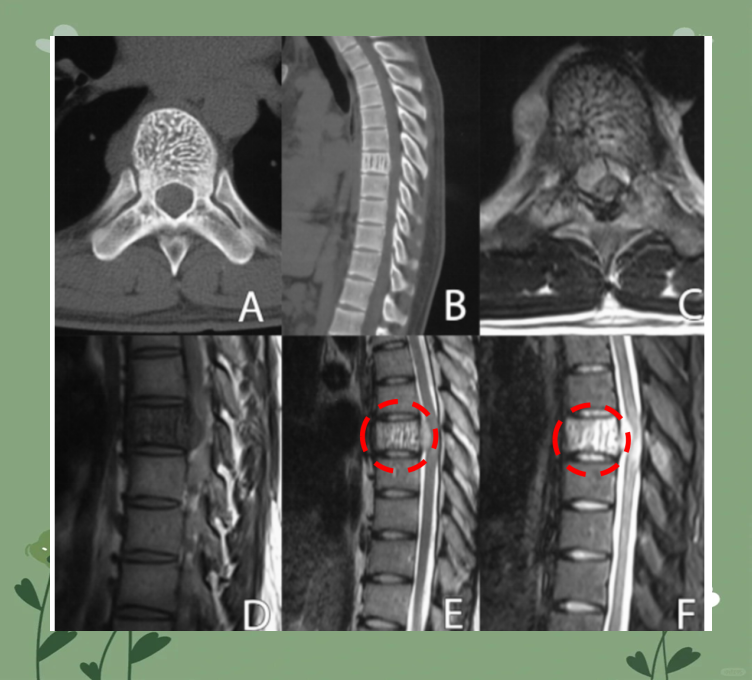

腰椎肿瘤是怎么回事?

CT检查表现为低密度影,CT值通常在120~70HU,边界清楚,与周围组织密度差异明显MRI检查具有较高的软组织分辨率,能更精准显示脂肪瘤与腰椎神经等结构的关系,脂肪信号在T1WI和T2WI上均呈高信号,是诊断腰椎脂...